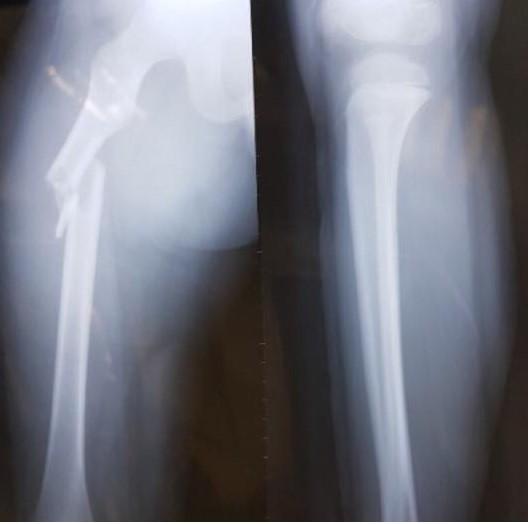

Hình ảnh khi xương đùi của học sinh Trần Chí Kiên được chụp X-quang. Ảnh: NVCC.

Sự việc bắt đầu vào ngày 1/12/2016, em Trần Chí Kiên bị ngã gãy xương đùi tại trường Tiểu học Nam Trung Yên.

Theo lời của Kiên, khi chạy về lớp, em va chạm với ôtô màu xanh nước biển đang di chuyển trong sân trường. Cháu nhận ra trên xe có cô hiệu trưởng và một giáo viên khác. Nữ hiệu trưởng đã phủ nhận điều này và cho làm khảo sát trong trường chứng minh mình vô can.